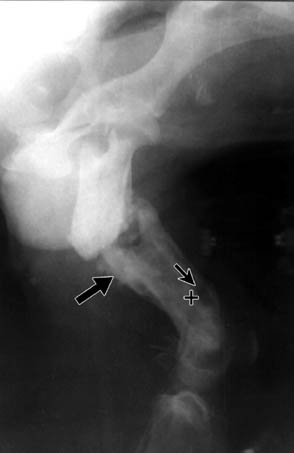

Between weeks 2 and 4, twenty dogs (90%) radiologically presented an irregular-shaped periosteal reaction with new bone formation (Fig. 1). A characteristic feature was that this occurred far from the fracture site, along the bone. In some cases, there were spicule-like formations with denser shadows (Figs. 2 and 5). In the event that a fragment of a comminuted fracture became necrotic, that is, that it turned into a primary sequestrum, it was surrounded by a dense shadow - a product of the periosteum (Fig. 3). During the development of osteomyelitis we observed a loosening of fixation implants in 15 dogs (68%). On radiographs, the condition was seen as zones of radiolucency around the implants, and after destabilisation of fractures - there was a formation of a callus in the place of mobility without healing (Fig. 4).

Fig. 3. Lateral radiograph of the femur in patient 10/26.03.91, four weeks after osteosynthesis. The crosses show the primary sequestrum, and arrows periosteal growth surrounding the sequestrum.

During that period, in 3 dogs (13%), a Brodie's abscess was formed - zones of radiolucency (osteolysis) with a round or irregular shape, surrounded by a denser ring (osteosclerosis). This radiological sign was characteristic of inflammations in the metaphyses of long bones (Fig. 5).

During the development of osteomyelitis, sequestra are formed, although not always. According to Velichkov (1983) they are partial and total, compact and cancellous. In our opinion, sequestra could be considered as primary and secondary also. Primary ones are with a size equal to that of a fragment, not involved in the healing process, while secondary ones are small and sometimes scarcely visible. The fragment turns into a sequestrum at the moment when there is no connection with the soft tissues, or where it is not well adapted or fixed to the principle bone ends.

The mechanisms of secondary sequestral formation are somewhat different. As a consequence of bone inflammation, thrombosis of the blood vessels in the haversian and Volkmann's canals occurred (Kahn and Pritzker, 1973). The supply to that area is impaired, it becomes necrotic and a sequestrum is formed.

Another radiological sign of osteomyelitis is osteosclerosis. It represents a reaction of bone, attempting to confine the infection. In most cases, it is apparent as a ring with a denser shadow and of different thickness. When a sequestrum is present, the sclerotic margin forms the so-called sequestral box. This occurs when the organism has fought the infection.